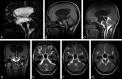

CE-MRC has been in use for the past 15 years and was reported to be a useful method in the evaluation of CSF disorders and hydrocephalus. The use of CE-MRC in conjunction with other MR imaging techniques has been shown to be effective in selected cases for the evaluation of several disorders of cerebrospinal system. CE-MRC has certain advantages over other cisternographic studies with fewer side effects if performed properly. Although intrathecal Gd administration is not widely accepted yet, several recent studies have reported the safety of small-dose intrathecal gadolinium injection. In this review, we describe CE-MRC and review recent applications in several clinical conditions.